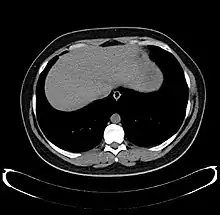

Diagnosis

The diagnosis of liver disease is made by liver function tests, groups of blood tests, that can readily show the extent of liver damage. If infection is suspected, then other serological tests will be carried out. A physical examination of the liver can only reveal its size and any tenderness, and some form of imaging such as an ultrasound or CT scan may also be needed.

Sometimes a liver biopsy will be necessary, and a tissue sample is taken through a needle inserted into the skin just below the rib cage. This procedure may be helped by a sonographer providing ultrasound guidance to an interventional radiologist.[69]

Axial CT image showing anomalous hepatic veins coursing on the liver's subcapsular anterior surface[70]

A CT scan in which the liver and portal vein are shown